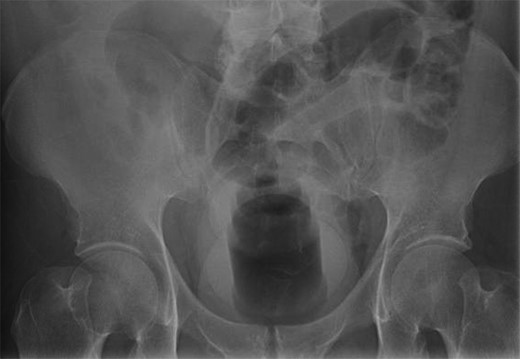

His medical history was significant for a previous irretrievable rectal foreign body 1 year earlier. This required transabdominal extraction, which revealed a baseball measuring 7.5 cm in diameter. At this most recent visit, an abdominal X-ray was ordered showing a large, mixed low and high-density foreign body fixed in the rectosigmoid colon (Fig. 1). Several attempts were made to remove the new object trans-anally, all of which were unsuccessful. At this time, the surgical team decided to perform exploratory laparotomy. Due to the severe inflammation and edema of the rectosigmoid (Fig. 2), as well as adhesions secondary to the previous abdominal surgery, a Hartmann’s procedure with creation of end sigmoidostomy was required. The object, a rubber chew toy, was successfully removed and measured 11 cm in length and 10 cm in diameter (Figs 3 and 4). The patient’s post-operative course was complicated by a prolonged ileus. He was discharged home on post-operative day 10 and recovered appropriately. Colostomy reversal was discussed and he was followed as an outpatient.

Abdominal X ray showing a large, mixed low and high-density foreign body in the rectosigmoid.